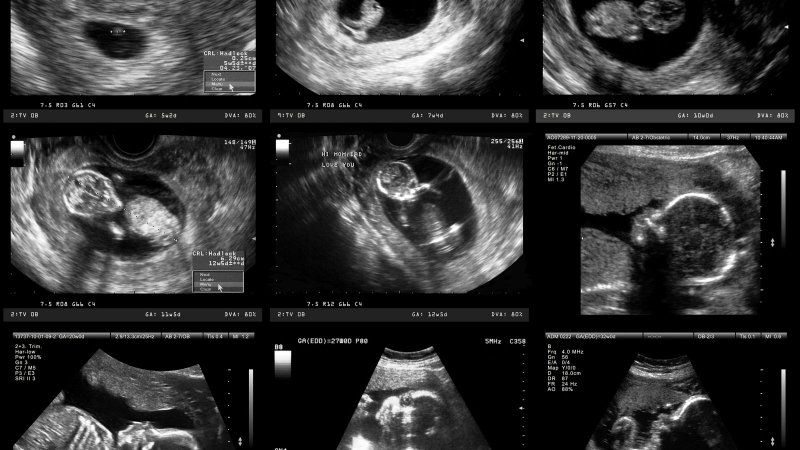

Để có thể có kết quả chắc chắn, bạn nên đến những cơ sở y tế uy tín để có thể siêu âm thai. Siêu âm thai là phương pháp chính xác nhất hiện nay để có thể xác định độ tuổi của thai nhi ngay cả khi bạn không nhớ chính xác chu kỳ kinh nguyệt của mình.

Khi thai được khoảng 7 - 9 tuần, bác sĩ sẽ thực hiện siêu âm để đo chiều dài đầu mông (hay còn gọi là CRL) của thai để tính ra ngày dự sinh cũng như tuổi thai hiện tại. Tuổi thai nhi được tính vào thời điểm này có độ chính xác rất cao, chỉ sai lệch trong khoảng 3 ngày.

Nếu bạn bỏ lỡ thời gian đầu này, bác sĩ có thể dựa vào các lần siêu âm sau để dự đoán ngày sinh. Tuy nhiên, càng về sau, thai sẽ càng lớn dẫn đến độ sai lệch sẽ càng tăng.

Bên cạnh đó, khám thai qua siêu âm cũng có ý nghĩa quan trọng không chỉ trong giai đoạn đầu mà trong suốt cả thai kỳ. Ngoài tuổi thai, bạn sẽ có thể biết được sự phát triển và tình trạng sức khỏe của thai nhi, qua đó có thể phát hiện sớm những bất thường hay vấn đề của thai.

Trễ kinh 20 ngày thai được mấy tuần tuổi? Cách tính tuổi thai chính xác 3 Tính tuổi thai qua hình ảnh siêu âm